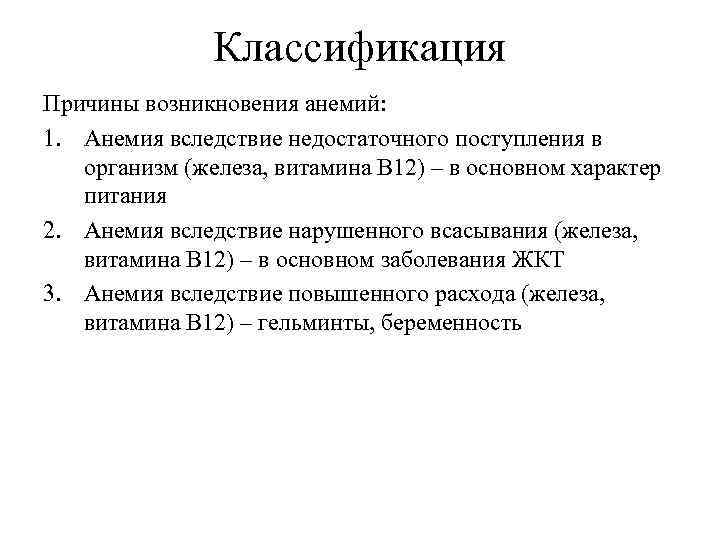

Классификация Причины возникновения анемий: 1. Анемия вследствие недостаточного поступления в организм (железа, витамина В 12) – в основном характер питания 2. Анемия вследствие нарушенного всасывания (железа, витамина В 12) – в основном заболевания ЖКТ 3. Анемия вследствие повышенного расхода (железа, витамина В 12) – гельминты, беременность